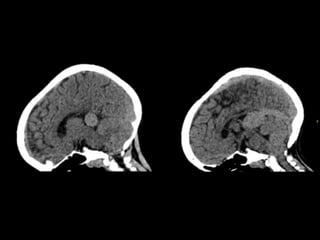

ESTUDIOS REALIZADOS:

TC CEREBRAL SIMPLE

08-06-2023.

TC SIMPLE DE CRANEO

08/06/2023

Hallazgos en TC

TC SIN CONTRASTE

o VPM ligeramente hiperdensa con el cerebro.

o Hidrocefalia.

o Hipodensidad y Ca++ de la sustancia blanca (SB)

subcortical ---> isquemia venosa crónica.

o Hemorragia intracraneal poco frecuente.

TC + C

o Realce vascular de arterias nutricias y VPM.

ATC

o Excelente definición angiográfíca de la MAVG